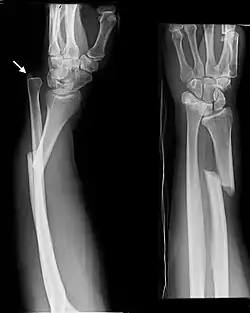

The Galeazzi fracture is a fracture of the distal third of the radius with dislocation of the distal radioulnar joint. It classically involves an isolated fracture of the junction of the distal third and middle third of the radius with associated subluxation or dislocation of the distal radio-ulnar joint; the injury disrupts the forearm axis joint.[1]

Galeazzi fractures are best treated with open reduction of the radius and the distal radio-ulnar joint.[3] It has been called the "fracture of necessity," because it necessitates open surgical treatment in the adult.[4] Nonsurgical treatment results in persistent or recurrent dislocations of the distal ulna.[1] However, in skeletally immature patients such as children, the fracture is typically treated with closed reduction.[1]